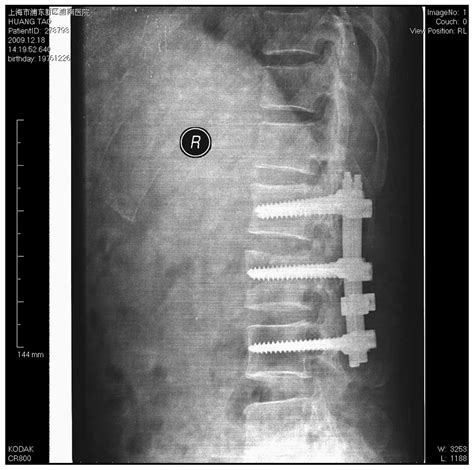

Spinal Fusion Permanently joining vertebrae with hardware. Unstable, complex, or traumatic fractures.

Surgical Interventions for Spinal Stabilization

When conservative methods fail to alleviate pain, or if the fracture results in neurological deficits or significant deformity, surgical Fractured Vertebrae Treatment becomes necessary. Modern spinal surgery has shifted toward minimally invasive procedures that offer faster recovery times and less tissue disruption.